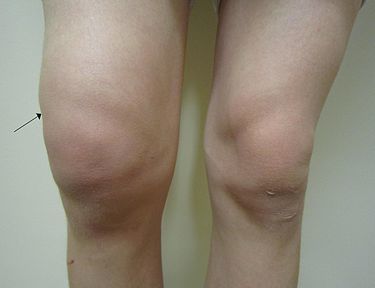

2. Derrame articular

1. añadidura

1. hiperemia+calor+dolor movilización o exacerbación de dolor

1. Crecimiento óseo en los márgenes de la articulación

1. manos y rodillas